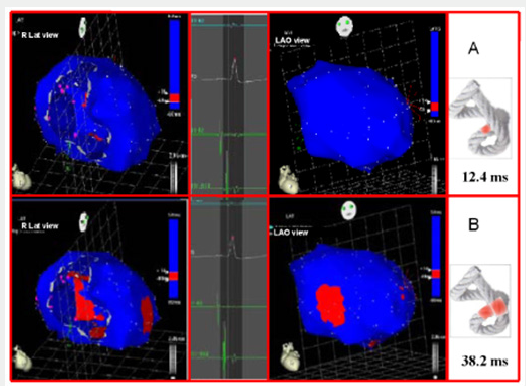

The EAM took an average of 20 minutes per patient. There were no complications Figures 3-5 illustrate endo and epicardial propagation of electrical activation. In all figures, the left panel shows the right lateral projection and the right panel the simultaneous left anterior oblique projection. The activated areas at each moment are seen in red. The lateral part represents the activation of the bands in Torrent Guasp’s rope model [1], where the depolarized zones are shown in red and previously activated zones in refractory period in blue. Below the rope can be seen the average propagation time of electrical muscle band measured in ms on the site analyzed (Table 1). This analysis was performed correlating the path of the stimulus with Torrent Guasp’s rope model of the cardiac band.

Left ventricular activation happens in the inter ventricular septum at 12.4ms±1.816ms after the start (Figure 3A). Next, following the anatomical arrangement of the descending band it spreads axially towards the ventricular apex. At that moment, the epicardial zone is also activated –the ascending band segmentevidencing radial activation in a region that can be termed as “segment intersection” (Figure 3B). It occurs on average after 25.8ms±1.483ms septal stimulation and 38.2ms±2.135 the onset of cardiac activation. This finding, as later discussed, modifies Torrent Guasp’s model and constitutes the electrical foundation of the mechanical phenomenon of ventricular twisting. Synchronously following the anatomical arrangement of the descendent band, activation moves axially towards the ventricular apex reaching the same on average of 58ms±2.0ms (Figures 4A & 4B) and (Table 1). From “segment intersection” the activation loses its unidirectional character and becomes more complex. Figure 4A shows 3 simultaneous wave fronts: 1) The distal activation of the descending band towards the apical loop; 2) the depolarization of the ascending band from the intersection towards the apex and 3) the activation of the ascending band from the intersection towards the end of the muscle band in the aorta.

Figure 3: A: Onset of left ventricular activation. The left panel illustrates the depolarization of the ventricular septum, corresponding to the descending band. In the right panel, the ventricular epicardium (ascending band) has not been activated yet. B. Simultaneous band activation. The activation progresses in the left ventricular septum along the descending band (axial activation) and at the same time propagates to the epicardium (radial activation), activating the ascending band.